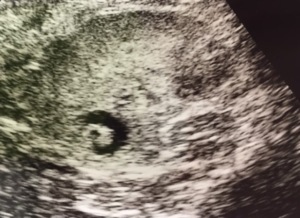

前立腺の組織の一部が変化し、水泡が溜まってしまう症状です。

肝臓にできる肝嚢胞、腎臓にできる腎嚢胞などと同様、あまり自覚症状はないのですが、たまに薄い血が尿に混じることがあります。

この場合、膀胱炎による出血と区別がつきにくく、止血剤などを使用しては止まってもすぐに再発を繰り返すケースが多いと思います。